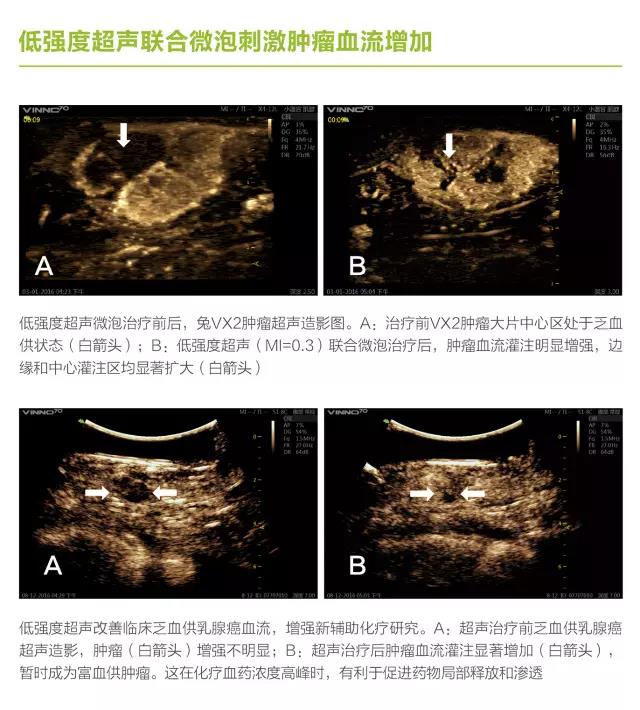

第三軍醫(yī)大學(xué)第二附屬醫(yī)院劉政教授長(zhǎng)期從事超聲空化研究,與飛依諾公司合作推出了在診斷超聲劑量下利用超聲空化效應(yīng)完成診斷與治療新機(jī)型 VINNO70超聲診療一體機(jī)。

VINNO70 超聲診療一體機(jī)在常規(guī)超聲診斷的基礎(chǔ)上,增加了V Flash超聲空化功能,多參數(shù)可調(diào)滿(mǎn)足了微氣泡諧振、膨脹、內(nèi)爆等的控制